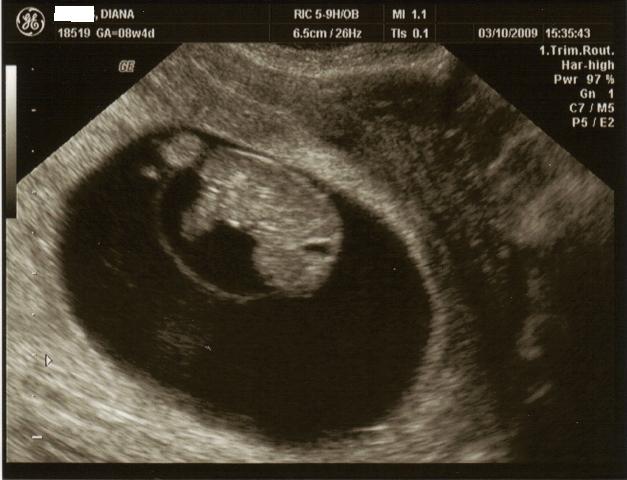

2nd doctor's visit!

Just got back. Snoopy's (I nicknamed the baby Snoopy) heartrate is 174 and got big!!!! doctor said he doesnt see anything wrong and doesnt need to see me until im 12 weeks.

here's my little snoopy!

He does look like a little Snoopy! Facing down! So cute!